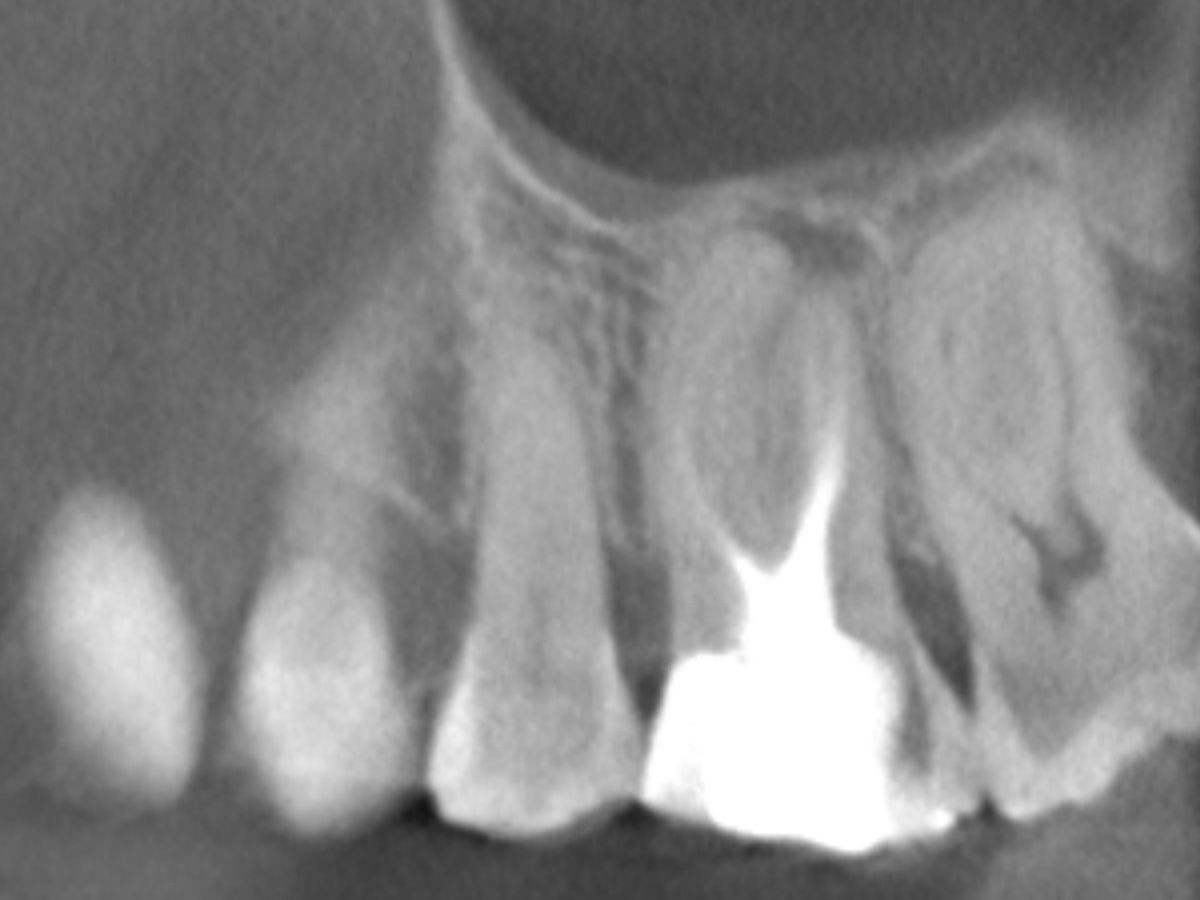

Der Patient stellte sich mit Aufbissschmerzen vor, wobei die klinische und röntgenologische Untersuchung eine symptomatische apikale Parodontitis an einem bereits wurzelkanalbehandelten Zahn 26 ergab. Die DVT-Aufnahme deutete auf einen unbehandelten zusätzlichen Kanal in der mesio-bukkalen Wurzel hin. Die Darstellung und Behandlung des mb2s sowie die Revision der bereits behandelten Kanäle erfolgte mit dem XP-endo® Rise Shaper bei einer hohen Umdrehungszahl von 2.500rpm.

Wurzelfüllung 26 exzentrisch

Wurzelfüllung 26 orthoadial